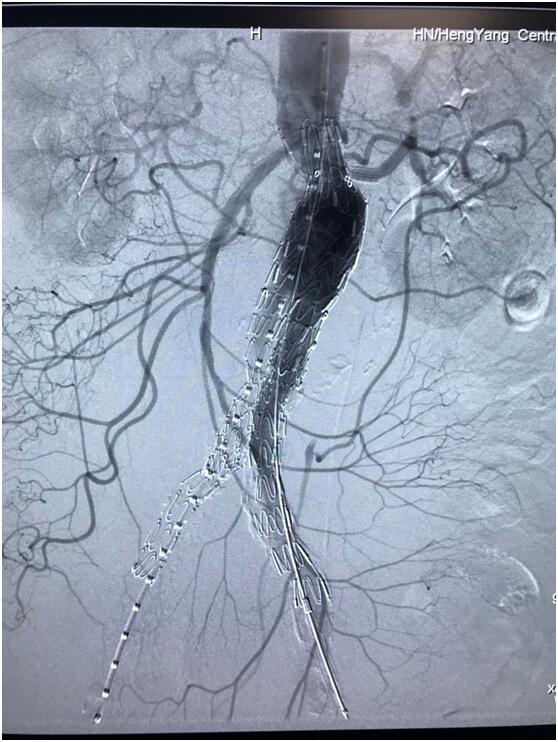

患者因腹部搏動(dòng)性腫塊行成已有4年,伴右下腹疼痛6小時(shí)入院,既往有高血壓病史,患者入院后血壓177/96mmHg,醫(yī)護(hù)人員隨即予以控制血壓、止痛處理,CTA檢查提示患者有腎下腹主動(dòng)脈瘤,合并心 、肝 、肺 、腎等重要臟器疾患,根據(jù) Laplace定律,動(dòng)脈瘤直徑越大壓力越大,老人動(dòng)脈脆弱,動(dòng)脈瘤隨時(shí)有破裂的可能性,其危險(xiǎn)性大。血管介入科排除各種困難,在麻醉科協(xié)作下行腹主動(dòng)脈瘤覆膜支架隔絕術(shù)(“褲衩”支架植入),手術(shù)持續(xù)了1個(gè)半小時(shí),患者術(shù)后安返病房,麻醉醒后露出了微笑,向醫(yī)務(wù)人員伸出大拇指。

血管介入科行腹主動(dòng)脈瘤覆膜支架隔絕術(shù)(“褲衩”支架植入)。圖3

4月20日,86歲李爺爺術(shù)后安返病房,麻醉醒后露出了滿意的微笑,還朝醫(yī)務(wù)人員伸出大拇指,此舉無(wú)聲勝有聲。